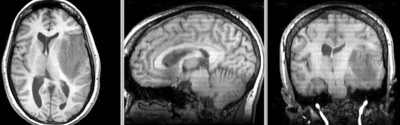

this is the fixed T1 reference image. lleft

Target Anatomical Ref. fMRI

• reference/fixed : T1 0.5 x 0.5 x 1 mm , 512 x 512 x 176

unregistered unregistered

after rigid registration after rigid registration

after non-rigid registration after additional BSpline non-rigid registration